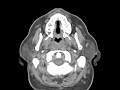

Angiomyolipoma (AML)

This young adult presented with fever and night sweats. On imaging we see mild symmetric enlargement of the cervical lymph nodes and diffuse enlargement of the lymphoid tissue comprising Waldeyer s ring which is composed of the nasopharyngeal adenoids, palatine tonsils, lingual tonsils. This patient had an abnormal peripheral blood smear and bone marrow biopsy with a diagnosis of acute myelocytic leukemia. Lymph nodes in leukemia have similar characteristics to lymphoma. They can be large, are usually non-necrotic, and relatively symmetric indicating a systemic process. Differential considerations for the enlargement of Waldeyer s ring include reactive tonsillar lymphoid hyperplasia as in HIV, squamous cell carcinoma, or extra-nodal non-Hodgkins lymphoma of Waldeyer s lymphatic ring which is the most common site.